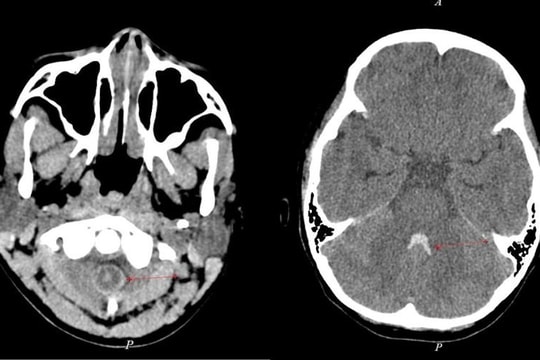

Không chủ quan với cơn đau đầu nhẹ thoáng qua

(QNO) - Ngày 4/5, Bệnh viện Đa khoa Gia Đình Đà Nẵng tiếp nhận bệnh nhân Đ.N. (10 tuổi) trong tình trạng tím tái, mất ý thức, ngưng thở.